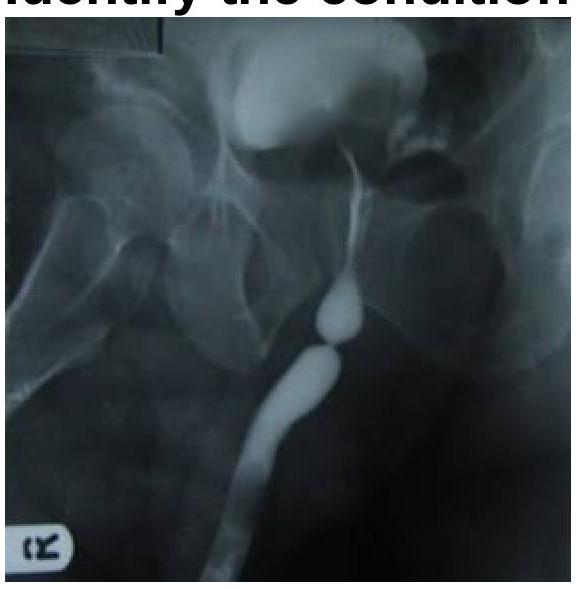

Question 3: Identify the imaging modality and the location of pathology shown in the image.

- A. MCU with Bulbar urethral stricture (Correct Answer)

Explanation: ***MCU with Bulbar urethral stricture*** - The image shown is a **Micturating Cystourethrogram (MCU)** because the bladder is filled with contrast and the urethra is being visualized during urination. - There is a clear **narrowing (stricture)** in the **bulbar portion of the urethra**, appearing as a segment with reduced caliber, consistent with a bulbar urethral stricture. *MCU with penile stricture* - While it is an MCU, the stricture is located in the **bulbar urethra**, which is proximal to the penile (pendulous) urethra. - A penile stricture would be seen further distally in the urethra. *RGU with membranous stricture* - This is an **MCU**, not a Retrograde Urethrogram (RGU), which is performed by inserting contrast from the urethral meatus. In an MCU, the contrast flows antegrade from the bladder. - A **membranous stricture** would be located more proximally, within the deep perineal pouch, between the bulbar urethra and the prostatic urethra. *RGU with prostatic stricture* - As mentioned, this is an **MCU**, not an RGU. - A prostatic stricture would be located within the **prostatic urethra**, which is much more proximal than the stricture seen in this image.